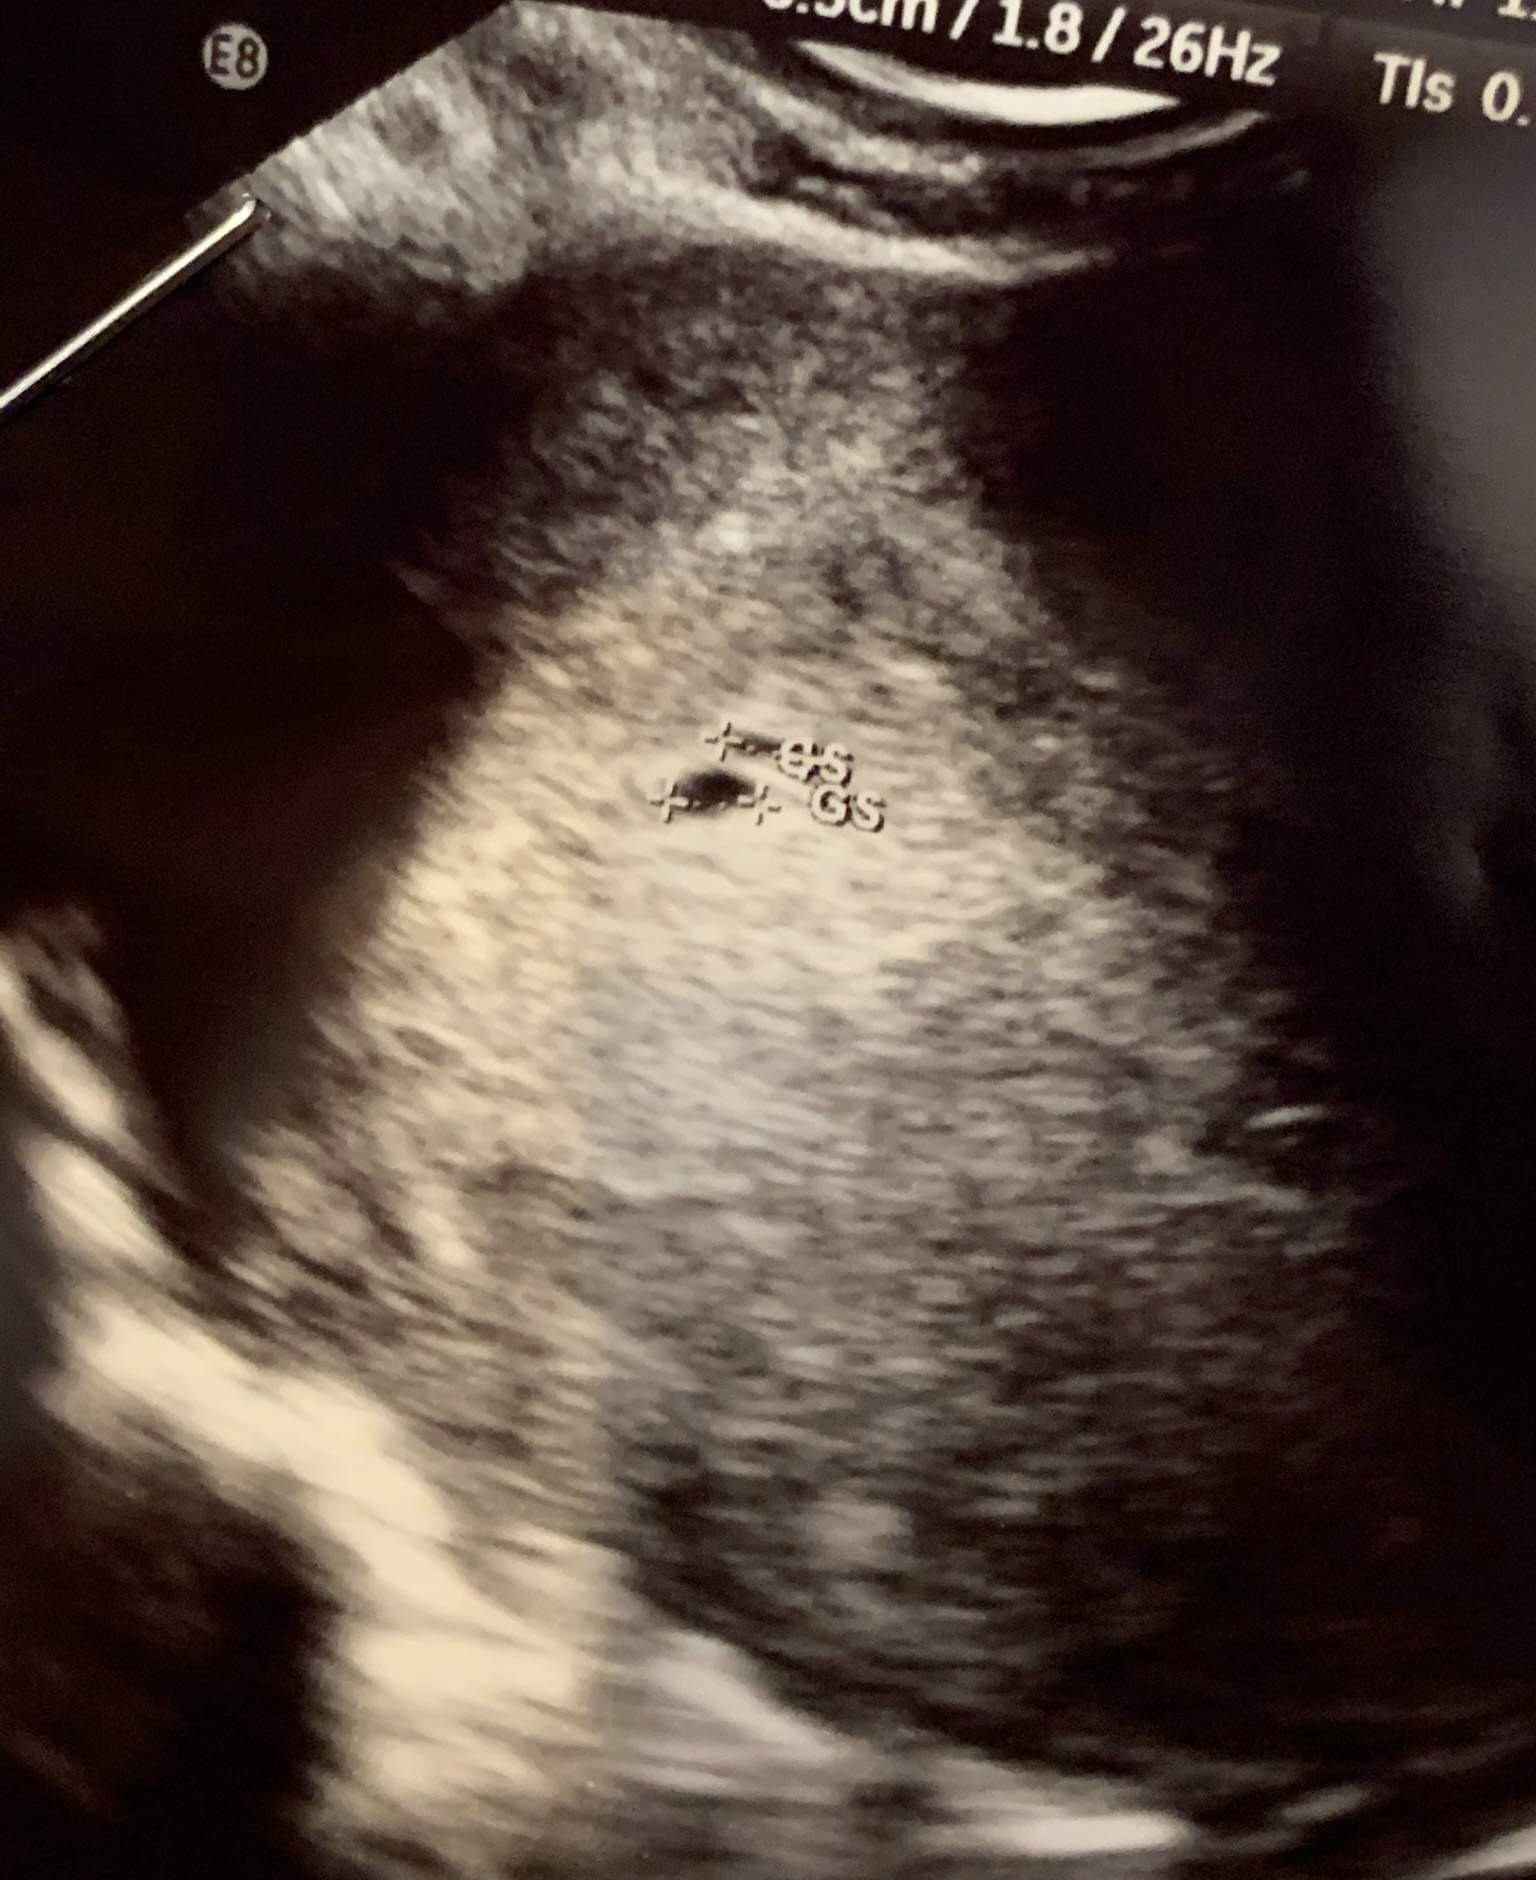

dziś byłam u gina i też jeszcze nic nie widać chodź tego się spodziewałam... Czy u was w okolicach 5 tygodnia coś już widać?